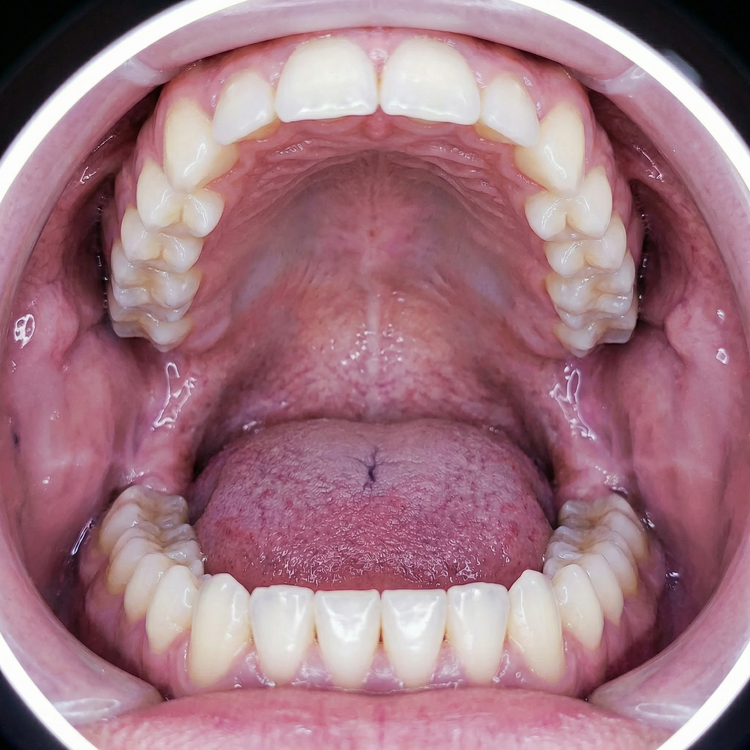

We recruited nine participants for our experimental test. To construct the biofilm, the participants were asked to avoid brushing their teeth for 100 hours.

On the fifth day, let's first look at the basic progress of the biofilm construction (using a biofilm staining agent):

The nine people were then divided into three groups of three. The first group was instructed to clean their mouths using only a toothbrush; the second group was instructed to clean their mouths using only a toothbrush and a tongue scraper; and the third group was instructed to clean their mouths using only the Tongueclear oral hygiene kit. Let's look at the cleaning results: